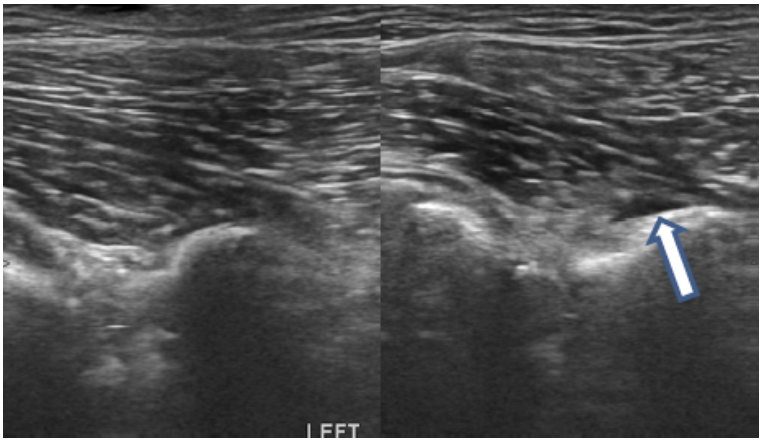

Clinical Evaluation of Iliopsoas Strain with Findings from Diagnostic Musculoskeletal Ultrasound in Agility Performance Canines – 73 Cases